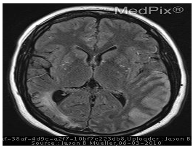

![]() | Modality | was this mri taken with or without contrast? which ventricle is compressed by the t2-hyperintense? was this mri taken with or without contrast? |